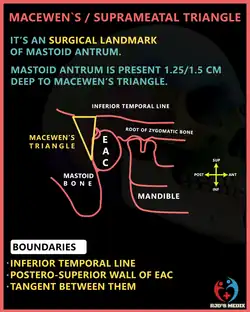

In the temporal bone, between the posterior wall of the external acoustic meatus and the posterior root of the zygomatic process is the area called the suprameatal triangle, suprameatal pit, mastoid fossa, foveola suprameatica, or Macewen's triangle, through which an instrument may be pushed into the mastoid antrum.

In the adult, the antrum lies approximately 1.5 to 2 cm deep to the suprameatal triangle. This is an important landmark when performing a cortical mastoidectomy.

The triangle lies deep to the cymba conchae.